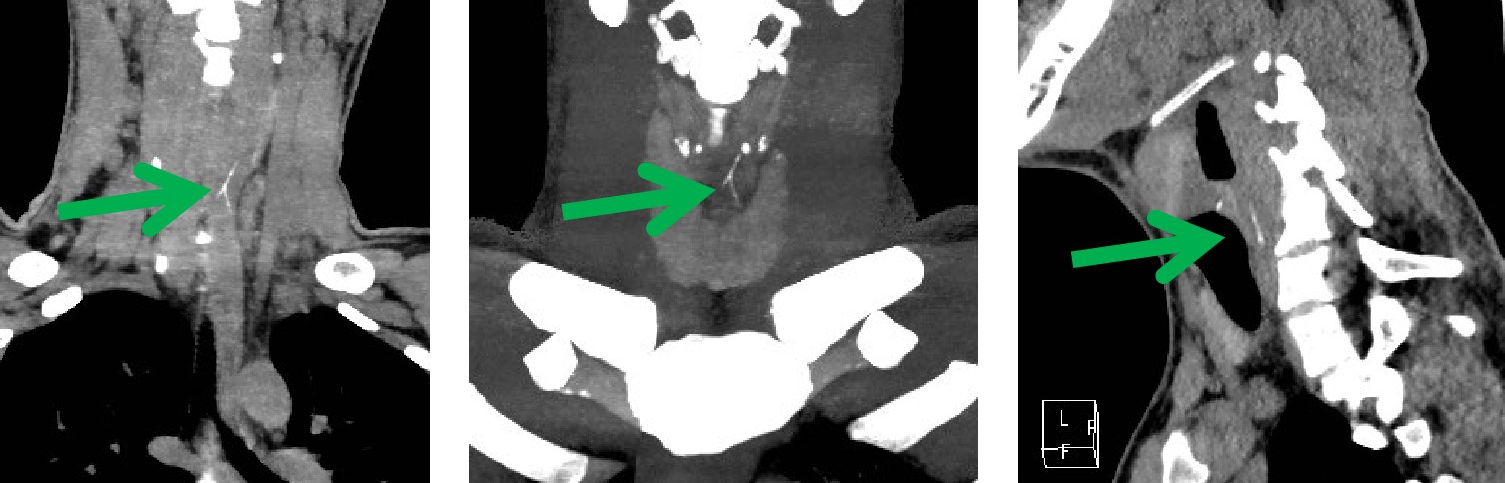

近日,我科来了一位十九岁的患者,一小时前吃鱼,一个不小心,把鱼刺咽下去了。感觉咽部不适异物感,急忙来21点游戏规则 就诊。先进行了喉镜检查 ,没有发现鱼刺的踪影。便连忙来到我科,进行食管异物CT扫描。此时,我科医生的火眼金睛该登场了,果然一下子就发现了罪魁祸首——狡猾的鱼刺。在患者的颈6椎体平面食道内,我们看到一个倒“Y”形的高密度影。我科医生又通过计算机后处理技术,很快这根鱼刺既直观又立体的展现在我们的眼前,鱼刺你终于藏不住了吧!

CT薄层重建图像结合后处理技术能多平面、多方位观察及定位,了解异物与食管壁、周围组织间的关系与损伤程度,主要重建方法包括多平面重建 (multiplanar reconstruction,MPR)、最大密度投影 (maximum intensity projection,MIP) 及容积再现 (volume rendering,VR)。

MPR、VR 及 MIP 多种重建方式的联合应用可对食管异物及早诊断,确定异物大小、形态、走向及位置,能多角度、任意方位地对组织器官进行观察和分析,直观、立体显示异物与周围组织结构的关系及有无并发症,为临床治疗方案的选择提供较大的指导意义,是诊断食管异物的可靠方法,已经成为食管异物诊断的首选检查方法。